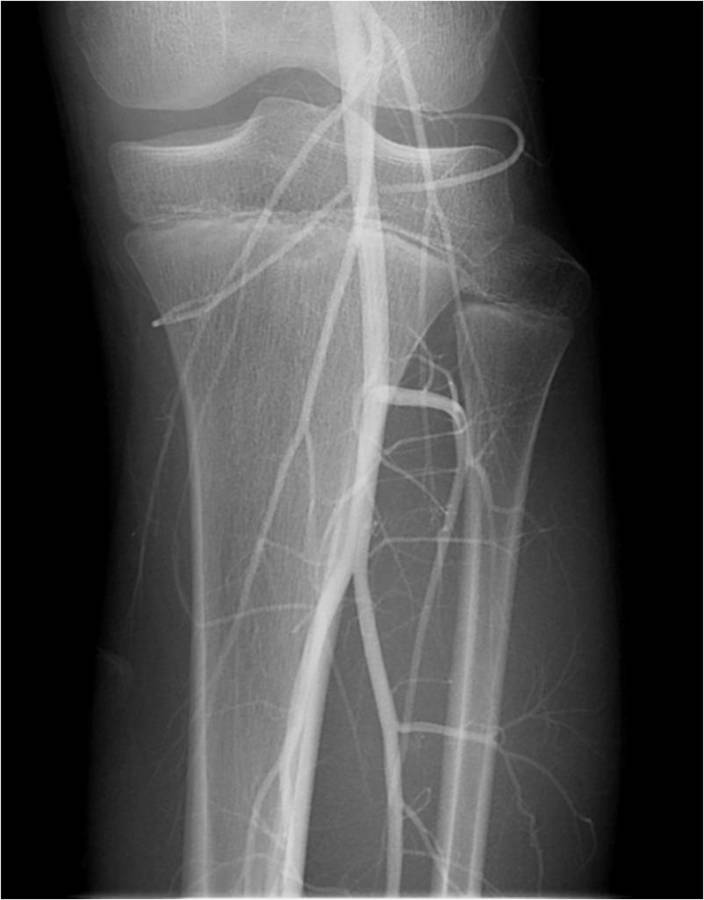

Gallery of Unlabled Radiographs from Lecture (Dr. French) - 2020

Click a thumbnail to enter the gallery display. Click the file name link at the bottom left of the gallery display to view the image at high resolution.